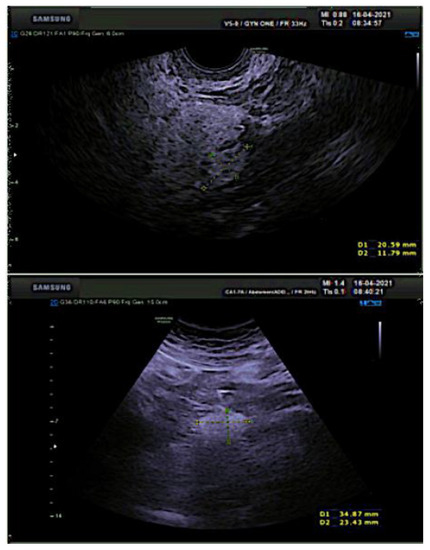

2. Case Report